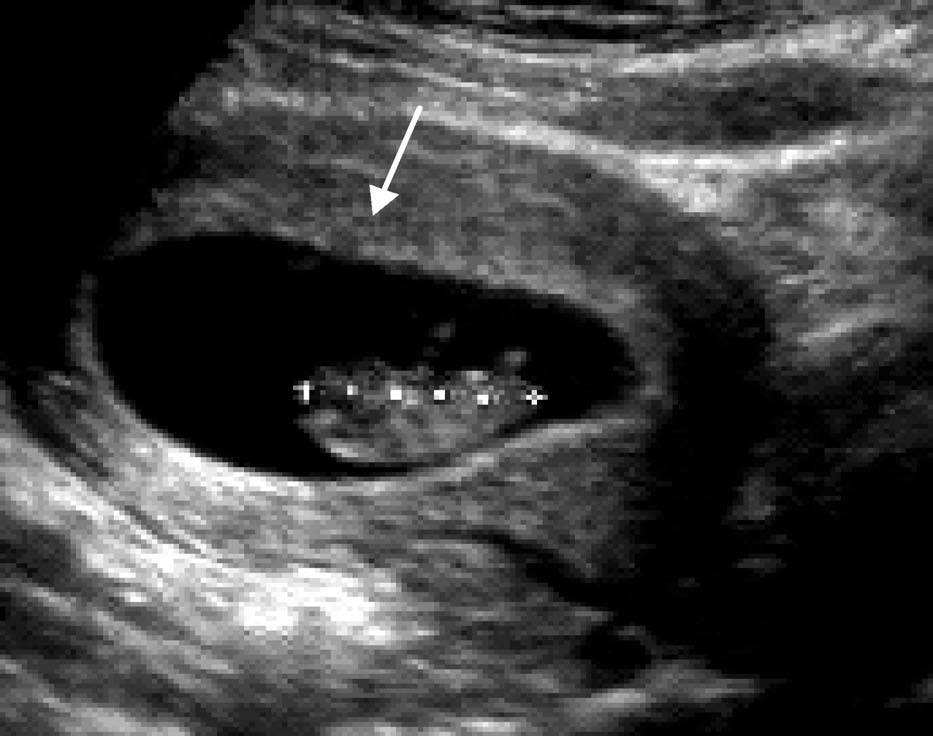

患者25 岁。停经35 天,尿HCG(+)。经阴道超声后位子宫纵切面:宫腔内见偏于一侧内膜的圆形囊性结构为胚囊(GS),称偏心圆;囊壁规则,呈中高回声,内部无回声;胚囊前后径2.7 mm;经阴道超声后位子宫横切面:测得胚囊横径为3.0 mm

超声诊断:宫内早早孕。